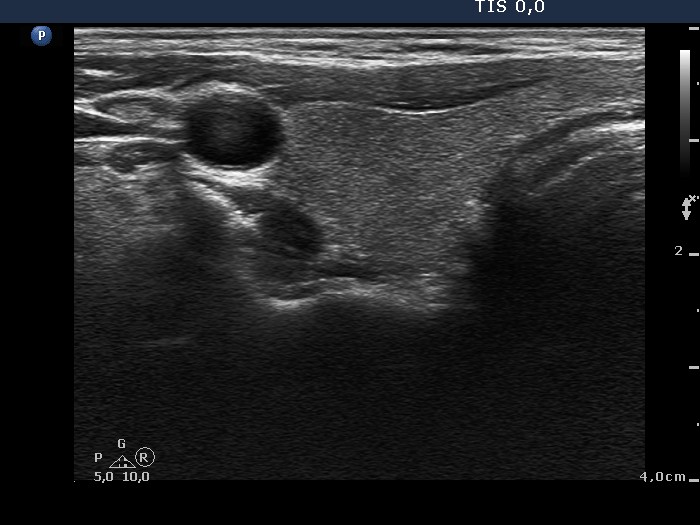

Extrathyroidal spread - case conp 032 (ultrasonographic picture 1)

Right lobe, transverse scan. This lobe is echonormal.